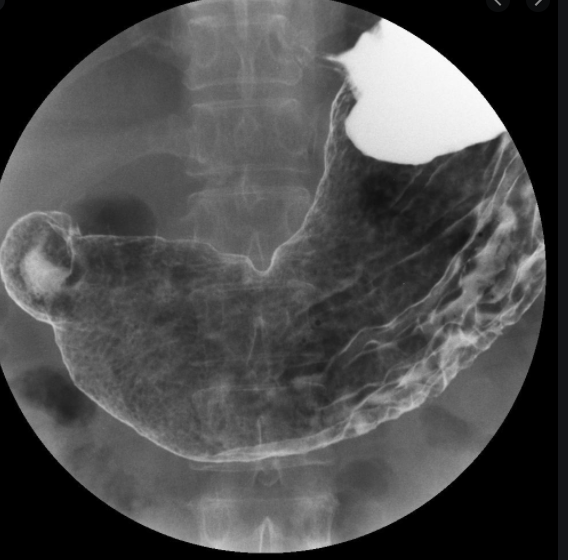

위혈관조영술은 위·십이지장의 상태와 질병의 유무를 확인하는 검사법으로, 잠을 자지 않고 검사한다는 장점이 있으나, 간접적인 방법이기 때문에 정확도가 다소 떨어질 수 있다. 위조영술의 장점 – 위내시경에 비해 불편함과 불편함이 적습니다. – 잠을 자지 않고 시행하기 때문에 노인, 허약자, 어린이에게도 시행할 수 있습니다.

위내시경과 위조영술의 차이점 위내시경은 작은 카메라 장치를 입안에 삽입해 식도, 위, 십이지장 부위를 관찰하고, 필요할 경우 조직을 제거해 이상 유무를 확인하는 검사법이다. 위벽에 조영제 용액을 코팅한 후 이를 이용하여 위와 십이지장의 이상 유무를 확인하는 검사로 정확도에서는 위내시경이 우수하다고 할 수 있습니다. 이전 이미지다음 이미지 원장 전원이 내과 전문의이며, 위장내시경 전문의 인증을 받은 밝은내일내과에서 원장이 직접 내시경, 초음파 검사를 시행하여 진료 우수병원으로 인증됨) 내시경 전문의가 편안하고 정확도 높은 위/대장내시경 풍부한 경험으로 / 폴립 제거 수술을 시행합니다. 밝은내과의원은 초음파치료 우수병원과 고혈압, 당뇨병 치료 우수내과의원으로 인정받고 있습니다. 밝은내과의원 홈페이지 (밝은내과의원 – 인사말) 밝은내일내과의원에서 체계적인 맞춤형 진료를 받아보세요. 금천구 시흥내과의원 내시경초음파대장내시경 굿 naeilclinic.modoo.at 밝은내일내과의원 밝은내과의원 오시는길 서울시 금천구 시흥대로 230 서평빌딩 3층(다이소빌딩) 이 포스팅 밝은내일내과의원에서 의료광고법 제56조 제1항에 의거 작성하였습니다.